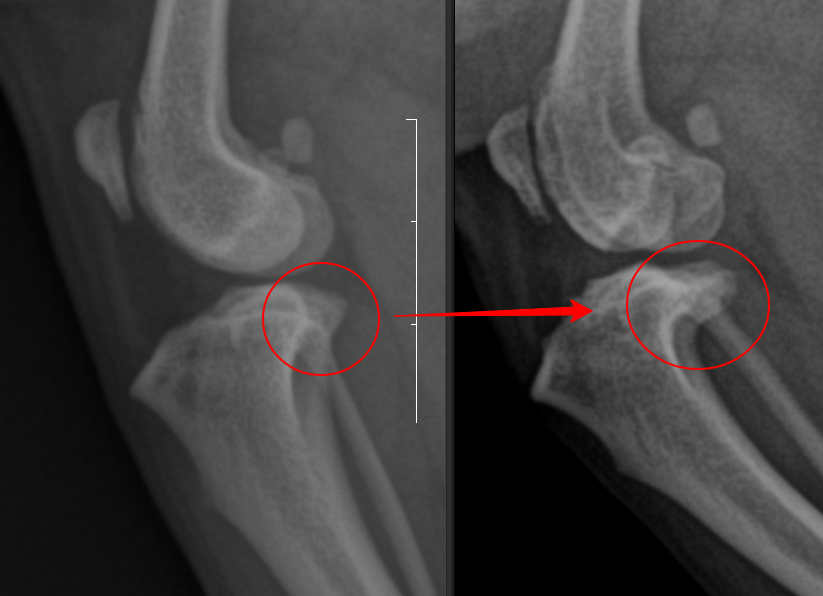

수술을 한 좌측 다리에서는 경미한 경골 조 면부 enthesophytosis가 관찰된다. 반면 수술하지 않은 우측 다리의 경우는 완전히 다른 예후를 보인다.

관절낭종창이나 관절의 심한 퇴행성 변화 양상은 차치하더라도 경골 조면의 후방의 골 증식양상이 뚜렷하며 이로서 경골의 TPL이 증가한 양상이 관찰된다. 이렇게 되면 십자인대에 가해지는 압력의 크기가 증가하여 십자인대가 파열할 가능성이 높으며 그 증거가 관절낭의 종창이다.